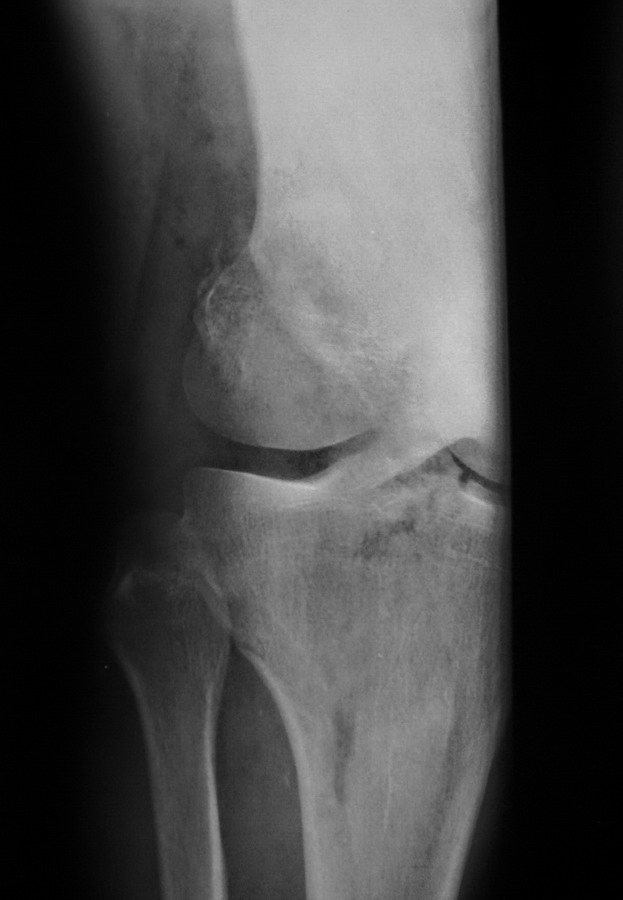

[Ortho] Нелеченный перелом Hoffa

Остеосинтез LCP пластиной